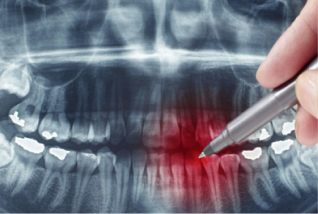

Ти безсумніву знаєш, що стоматолог – це лікар, який займається хворобами, пов’язаними з ротовою порожниною, зубами та щелепно-лицьовою областю. На жаль, відвідування дантиста не є обов’язковим для вступу до дитячого садочку, школи чи професійного медичного огляду. Хоча стан слизової та зубів значно впливає на весь організм. Перед кожною людиною рано чи пізно стає питання, як часто потрібно відвідувати стоматолога.

1. Стоматолог-хірург. Проводить хірургічні втручання – видалення зубів та коренів.